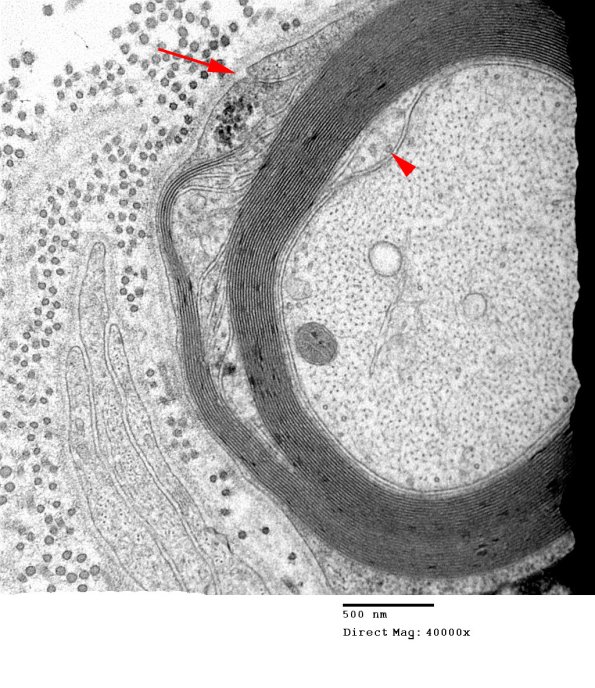

The external origin of the SLC in this case appears to involve the external mesaxon (arrow). The internal layer reaches the adaxonal space (arrowhead). (Electron micrograph)